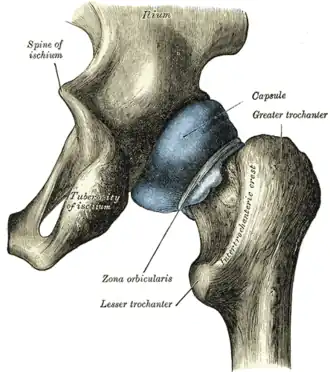

In human anatomy, the lesser trochanter is a conical, posteromedial, bony projection from the shaft of the femur. It serves as the principal insertion site of the iliopsoas muscle.[1]

The summit of the lesser trochanter gives insertion to the tendon of the psoas major muscle and the iliacus muscle;[3] the lesser trochanter represents the principal attachment of the iliopsoas.[1]

The intertrochanteric crest (which demarcates the junction of the femoral shaft and neck posteriorly) extends between the lesser trochanter and the greater trochanter on the posterior surface of the femur.[1]